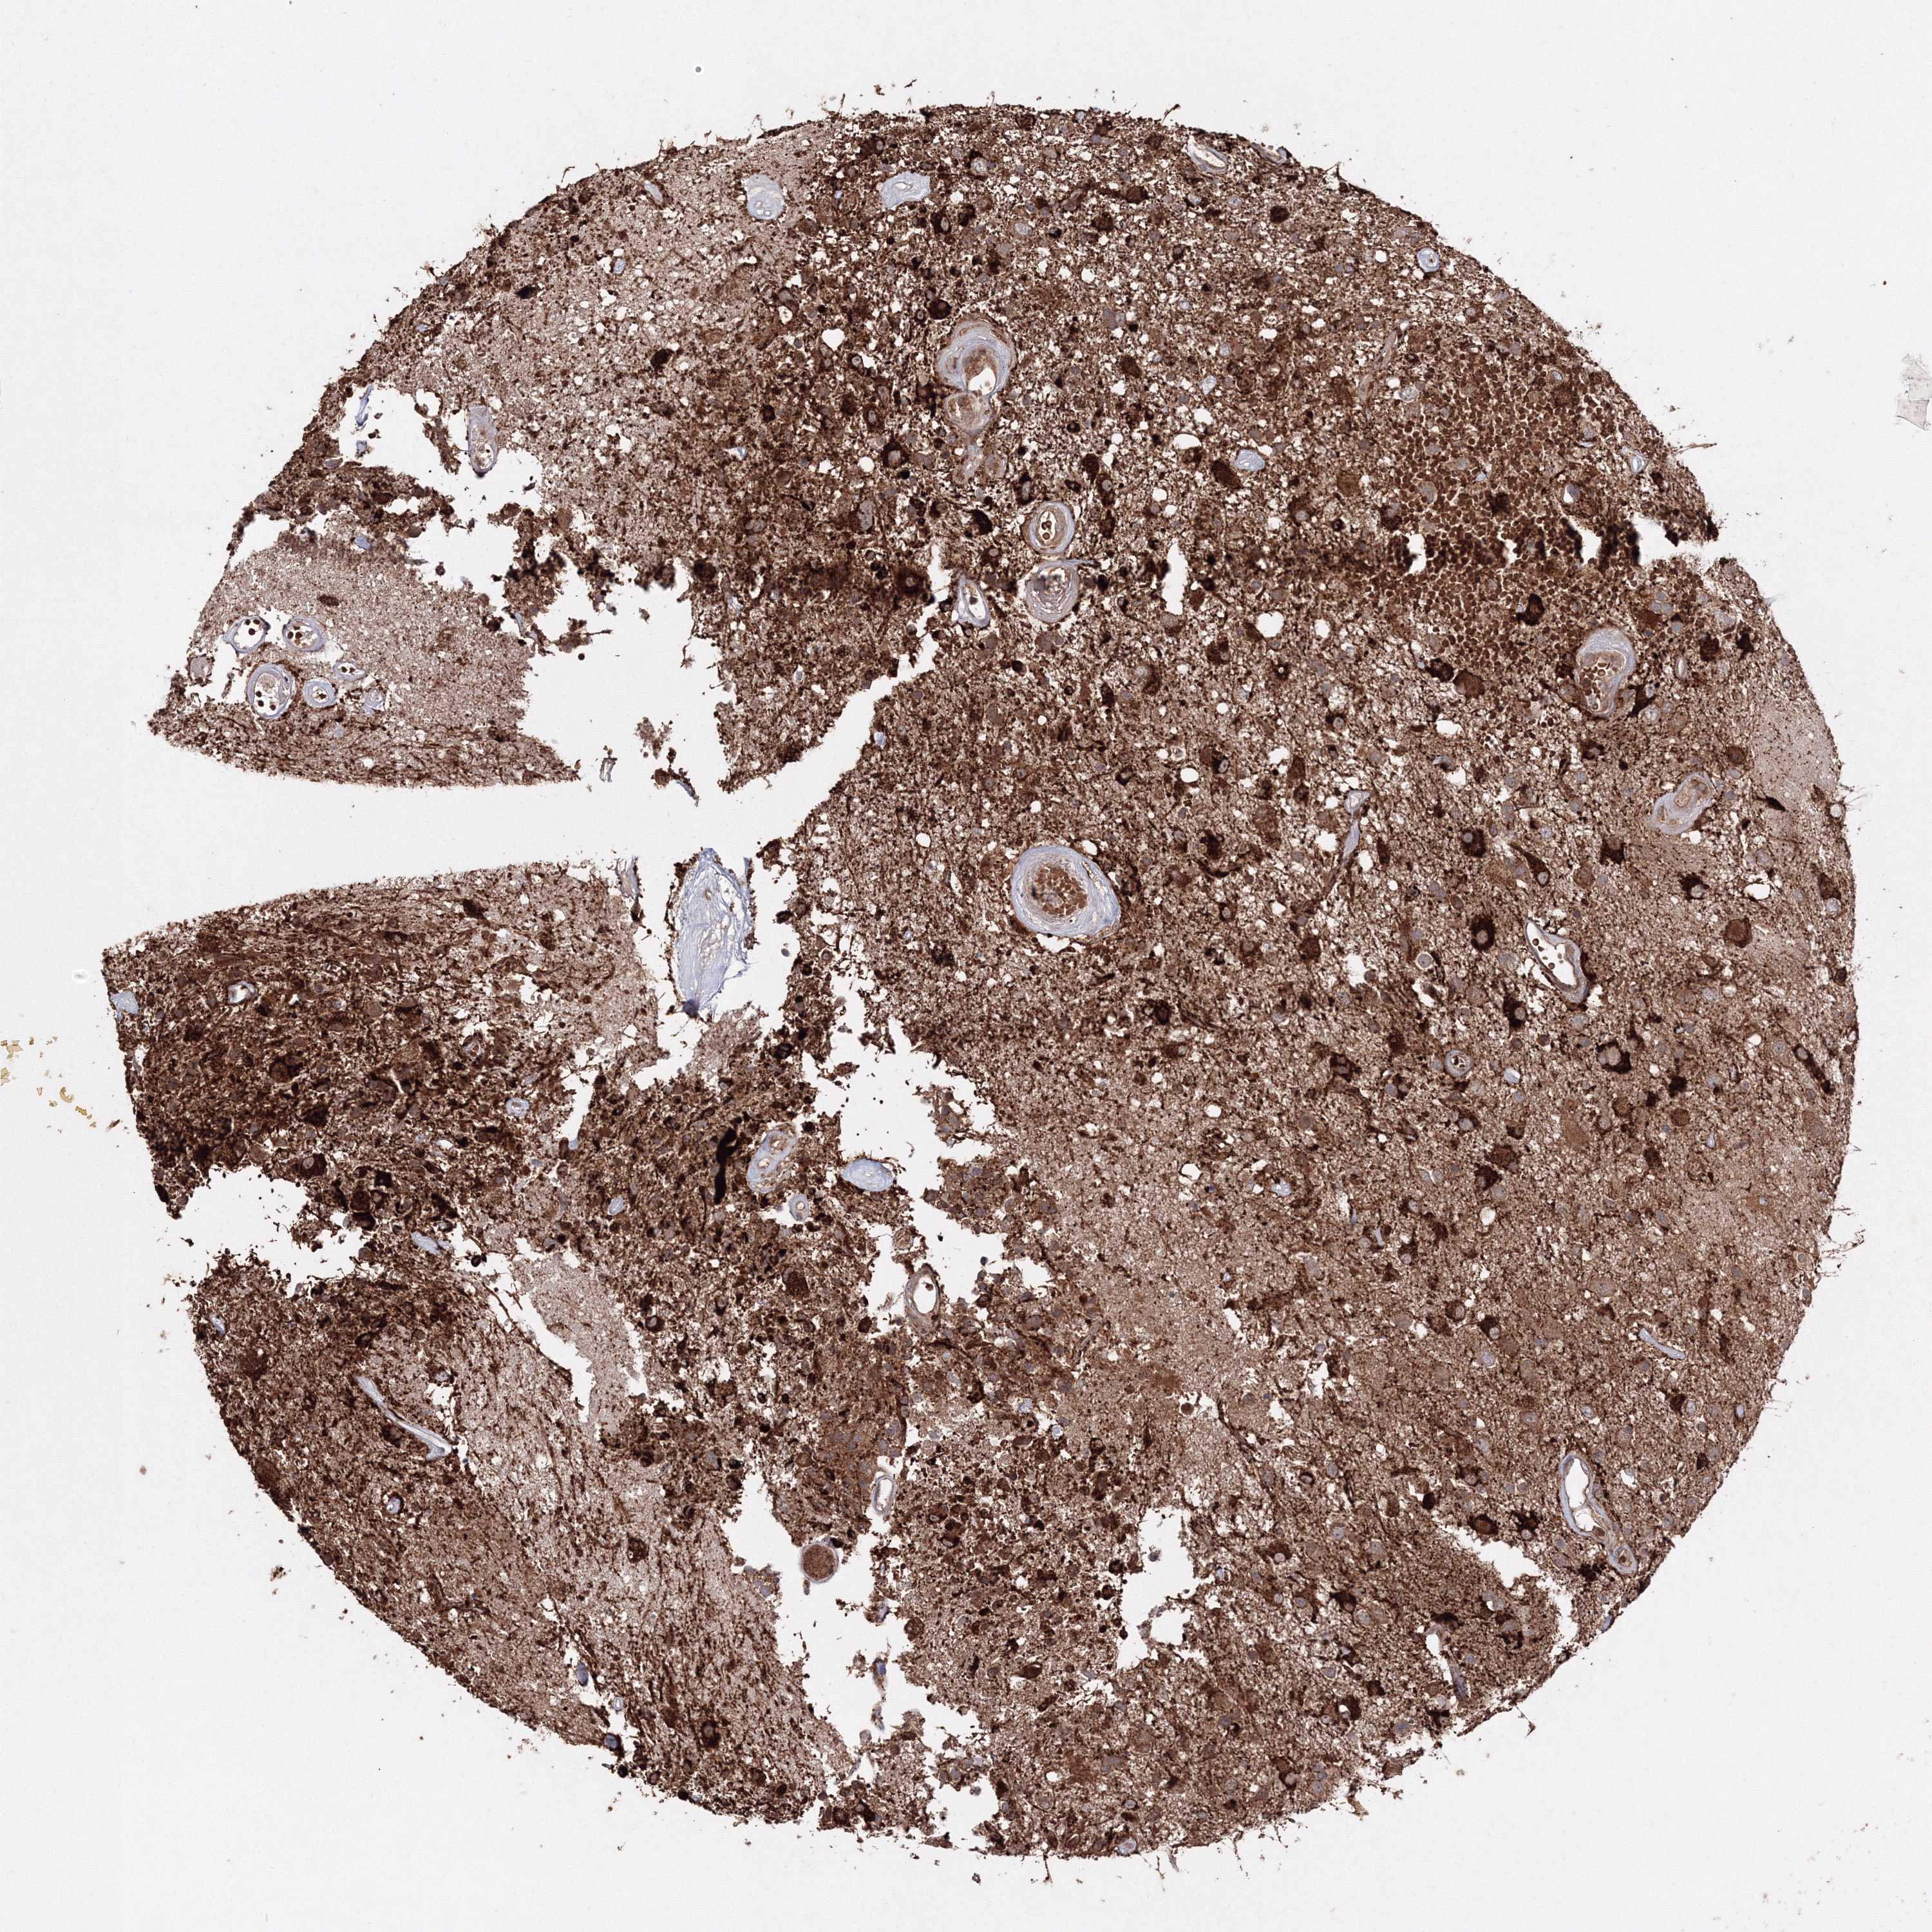

GLIOMA - Protein expressioni

A mouse-over function shows sample information and annotation data. Click on an image to view it in a full screen mode. Samples can be filtered based on level of antibody staining by selecting one or several of the following categories: high, medium, low and not detected. The assay and annotation is described here.

Note that samples used for immunohistochemistry by the Human Protein Atlas do not correspond to samples in the TCGA dataset.

Antibody stainingi

Antibody staining in the annotated cell types in the current human tissue is reported as not detected, low, medium, or high, based on conventional immunohistochemistry profiling in selected tissues. This score is based on the combination of the staining intensity and fraction of stained cells.

Each image is clickable and will lead to virtual microscopy that enables deeper exploration of all samples and also displays staining intensity scores, fraction scores and subcellular localization as well as patient and tissue information for each sample.

Antibody HPA037525

Antibody HPA037526

Glioma, malignant, Low grade

Glioma, malignant, High grade

Glioblastoma, NOS